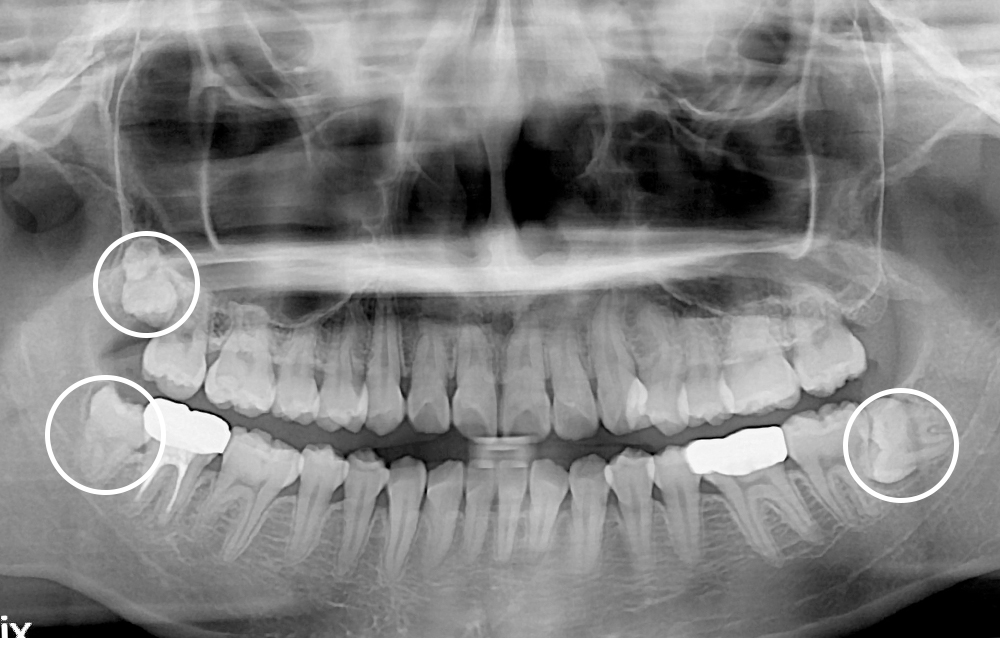

[사랑니] 매복 사랑니 발치

치료전 : 2019-02-13